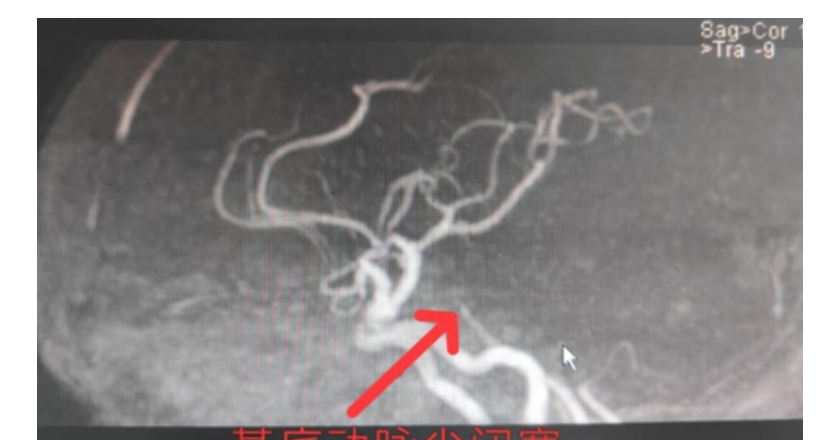

急性脑梗死介入取栓是怎么回事

急性脑梗死

怀疑急性脑梗死,该查核磁还是CT?你知道吗

CT 急性脑梗死 核磁